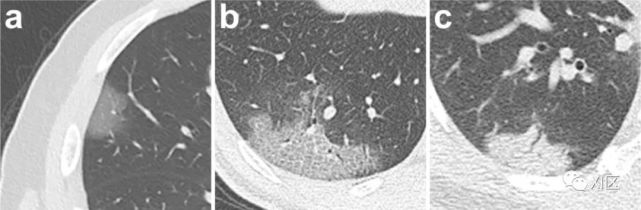

图18 64岁女性,在七月份出现疲劳、呼吸困难和喘息。因慢性阻塞性肺疾病接受了六天的治疗,但她因精神错乱和腹泻转诊入院。入院诊断,严重发热伴血小板减少综合征。胸部CT显示磨玻璃影,提示非心源性肺水肿或病毒性肺炎。这是第一例以呼吸困难和喘息开始的严重发热伴血小板减少综合征。

入院时胸部影像学表现。(a) 胸片显示双侧上肺野对称性浅磨玻璃影(GGOs)。胸部CT扫描也显示(b)双侧上肺野的GGOs和(c)肺气肿改变(箭头)和(d)支气管扩张(箭头)。